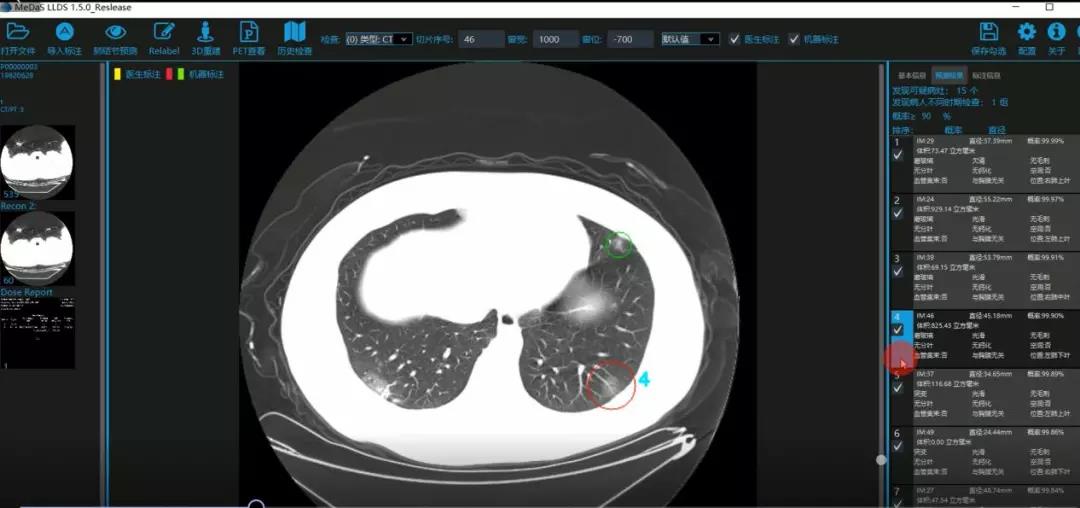

西电足球赌注网站智能软件与系统新技术研究所副教授张亮的爱人是西安交通大学第二附属医院抗疫一线的影像科医生,疫情发生以来,他们讨论最多的就是新型冠状病毒感染者的早期诊断问题。作为一名医护家属,身为高校科研工作者,张亮深知快速准确地诊断新冠肺炎早期患者对控制和防治疫情的重要性和挑战性。他与团队成员主动出击,通过远程网络会议,在前期医学影像处理的研究基础上加速科研攻关,反复讨论方案,屡次设计模型,与上海宽带技术及应用工程研究中心、上海交通大学医公司附属瑞金医院等合作单位的人员多次标注整理患者肺部CT影像数据到深夜。与此同时,他们依托上海瑞金医院、西安交通大学第二附属医院等的新冠肺炎疑似、确诊患者肺部CT影像,通过综合分析新冠肺炎患者的肺部CT影像特点(磨玻璃、体积大小、位置等特征),张亮团队加快技术攻关,设计开发了基于深度学习的新型冠状病毒的早期检测筛查模型系统。

对应新冠肺炎CT病灶检测效果

令人欣喜的是,通过对实际门诊数据排查测试,该模型可以减轻医护人员近80%的工作量,新冠肺炎患者的检测召回率超过95%。目前,模型系统正在进行最后的调试工作,很快投入到“战疫”一线,缓解医护人员紧缺、确诊检测工作耗时较长等问题,减少医护人员的工作时间和劳动强度,提高工作效率。